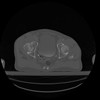

27 CUERPO,CE,Axial,3.0,CUERPO,,